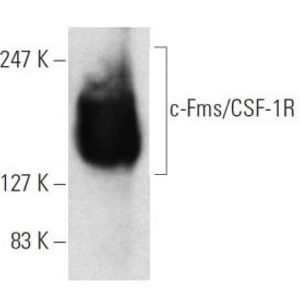

AUG 07, 2023CancerAn exciting new cancer drug has recently entered into a phase 1 clinical trial supported by promising pre-clinical work. ...